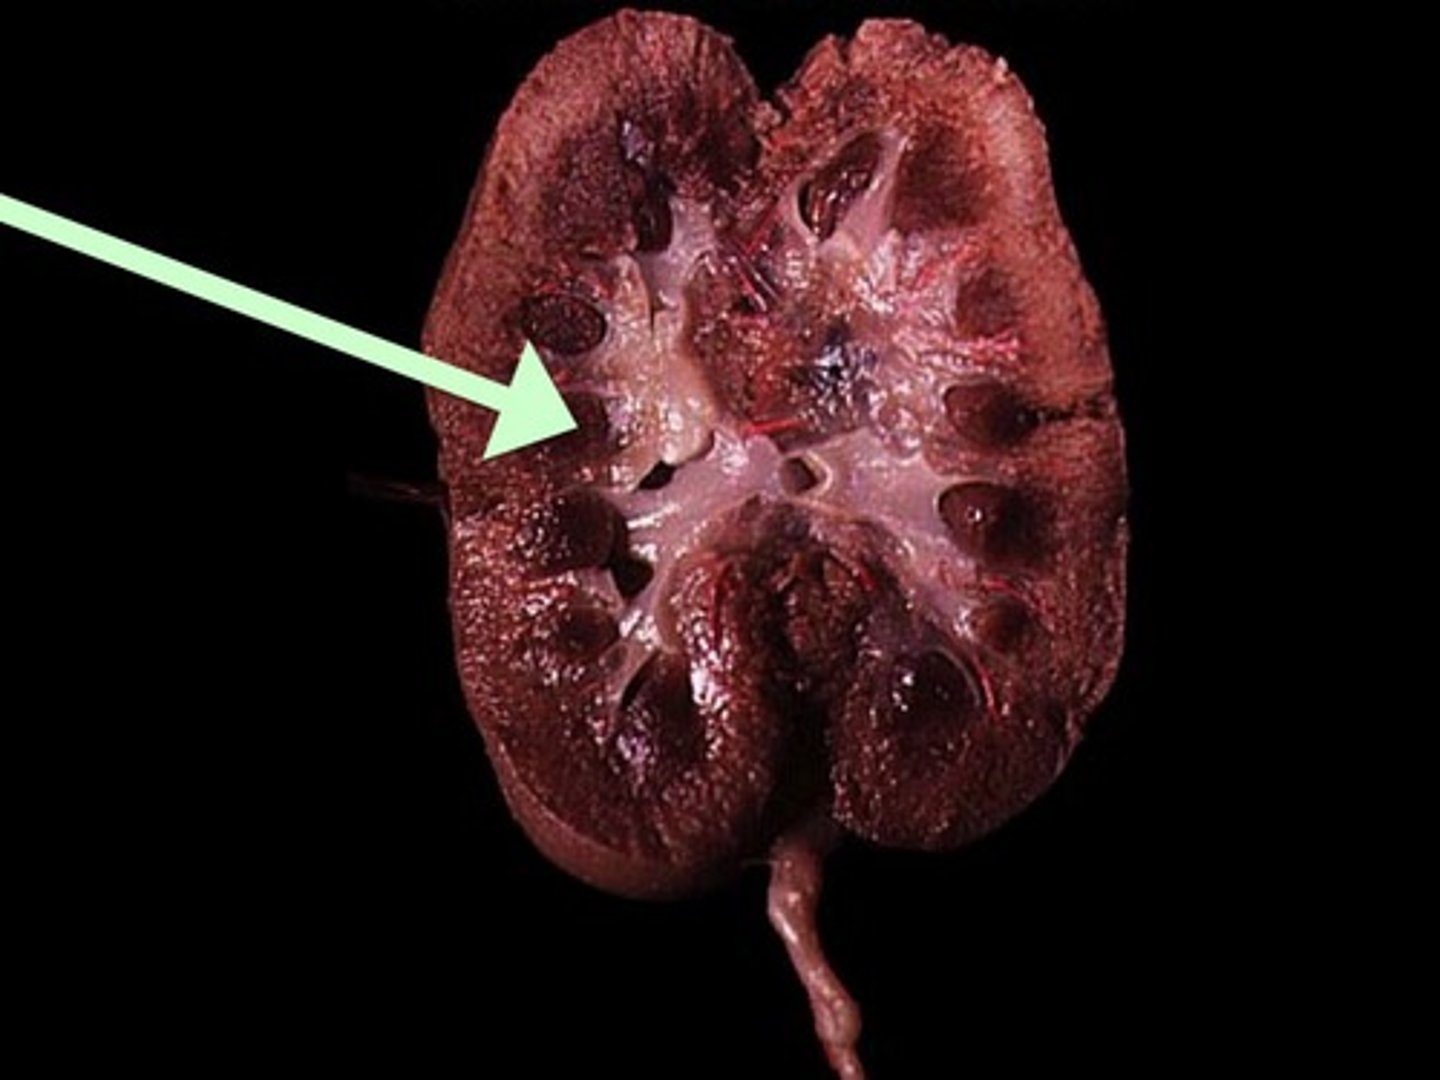

Renal Cortex

Renal Medulla

Renal Pyramid

Renal Column

Renal Pelvis

Ureter